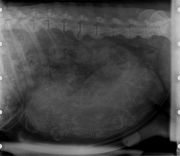

• Diagnostic de gestation (échographie et radiographie)